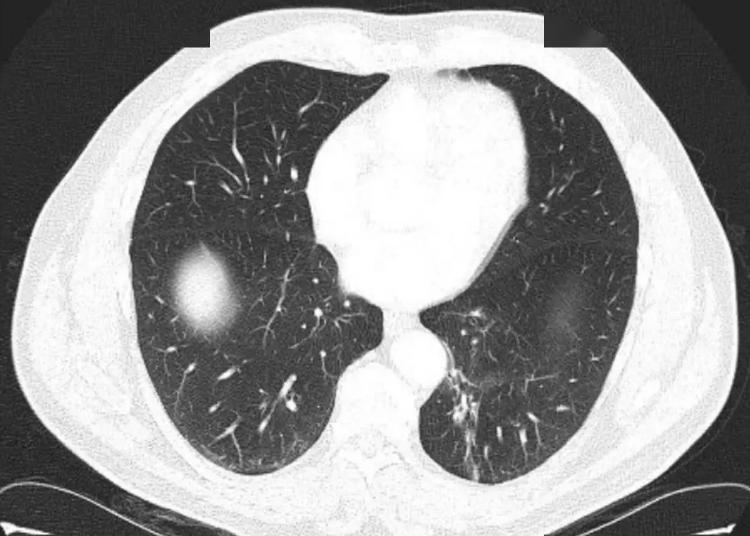

“心怎么这么大!”湖南长沙,一男子5年来,总是不断的咳嗽、咳痰,去了多家医院检查,得出的结论都是“肺部感染”,但病因却找不到!最近男子又开始咳嗽,这次他想起来,小时候曾不小心吸入过一个笔套。网友:白遭这么长时间的罪! 不知道大家上学时,有没有咬笔杆的习惯,常常把笔的末端咬碎,有时还可能会将笔帽吞下去,非常的危险,但当时年纪小,也不敢和家里人说,殊不知,这却可能影响你未来的人生。 据媒体12月19日的报道,十多年前,男子还在上小学,当时他非常调皮,喜欢研究各种东西,有一次,他将签字笔的笔帽放在鼻孔里,结果一个不小心,给吸到了气管里! 小孩子不懂事,发生这种事不知道有没有危害,最后也没有给家里人说,就这样,这个笔帽一直在男子的气管里,陪伴着他长大。 可是这个笔帽终究还是带来了危害,5年前,男子就经常咳嗽不止,虽然辗转去了很多医院,但是始终没有治好。 前不久,男子的咳嗽又变得厉害起来,这次医生做了详细的检查,发现他的气管里有一个异物,就是它导致的肺部感染。 男子仔细回忆,这才想起来小时候干的事,最终医生通过手术,将这个笔帽取了出来,随后经过一段时间的治疗,男子已经康复出院! 家长们一定要教育孩子,如果不小心吃了异物,务必及时告知家长,这样才能尽快的解决问题,不然很可能酿成悲剧。 信息来源:《21岁小伙10余年前不慎吸入的笔套,终于取出!》湖南日报